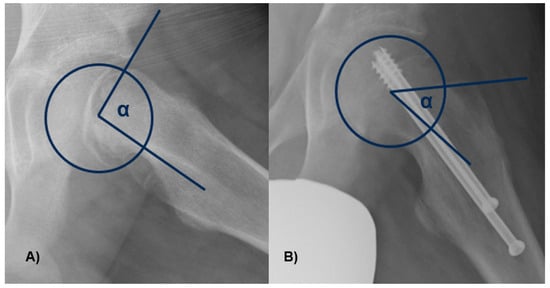

The α angle was measured between the axis of the femoral neck and the line extending from the central part of the femoral head to the location where the distance from the central point of the femoral head to the outer edge surpassed the femoral head’s radius (Figure 4). Slippage of the femoral head will occur at a higher α angle.

Figure 4.

The α angle was measured between the axis of the femoral neck and the line from the center of the femoral head to the point where the distance from the center of the femoral head to the peripheral contour of the femoral head exceeded the radius of the femoral head. In figure (A), there is an angle greater than 90°, with neck deformity, while in figure (B), the angle and the deformity are lessened.